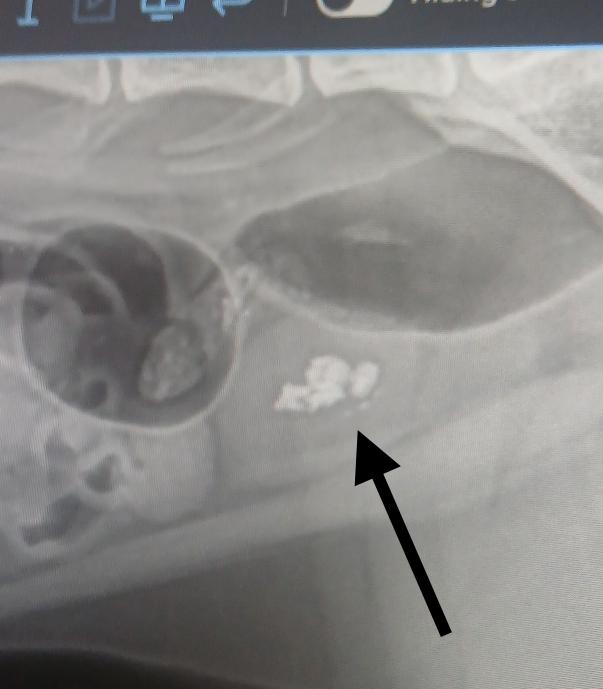

Meet Attie. This sweet sweet boy has had a rough go of it as of late. His elderly female owner was hospitalized, leaving him alone, subsequently passed away and he was surrendered by a relative. It was clear almost immediately that something was very wrong with Mr Attie. He did not want his back half of his body touched and would absolutely scream when using the litter box. He was also quite reactive and aggressive at times, clearly in pain. He was taken to the vet and found to have four very large bladder stones, which were surgically removed. Surgery was June 3rd.